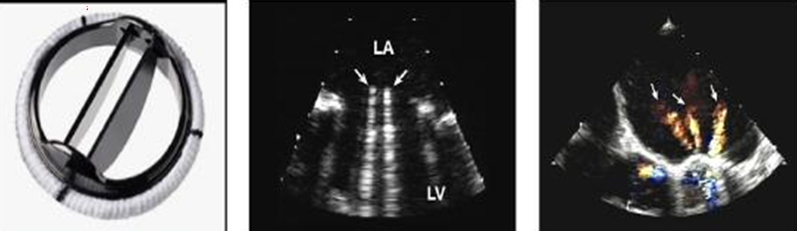

what valves do these represent?

mechanical (except c)

a. ball in cage

b single disc (bjork shiley)

d. double disk (st jude)

what is this?

bileaflet (st jude)

single leaflet (bjork shiley)

ball in cage (starr edwards)

how many orifices do prosthetic bileaflet (st judes) valves have?

3 orifices (3 color jets)

where do we sample velocities?

there are 2 large orifices and one smaller.

sample flow from the smaller orifice with higher velocities